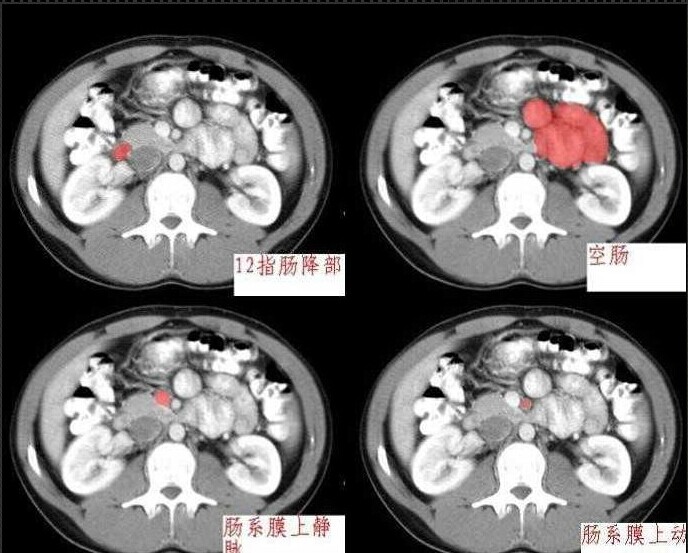

十分钟学会腹部CT解剖(多图)